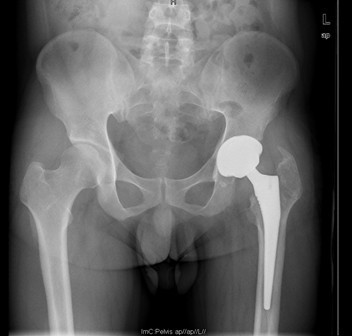

患者男,40岁,因“左股骨头股骨颈骨折切开复位内固定术后2+年”入院,患者2+年前因车祸致左股骨头、颈粉碎性骨折于我院就诊,行左股骨头股骨颈骨折切开复位空心钉+可吸收镙钉内固定术,术后恢复良好出院。术后7月后扶双拐活动。6月前患者无明显诱因出现左髋部疼痛,以负重时为重,后患者只能扶双拐活动。现患者为进一步治疗入我院。

诊断:左股骨头股骨颈粉碎性骨折切开复位内固定术后坏死 治疗:择期行关节置换术